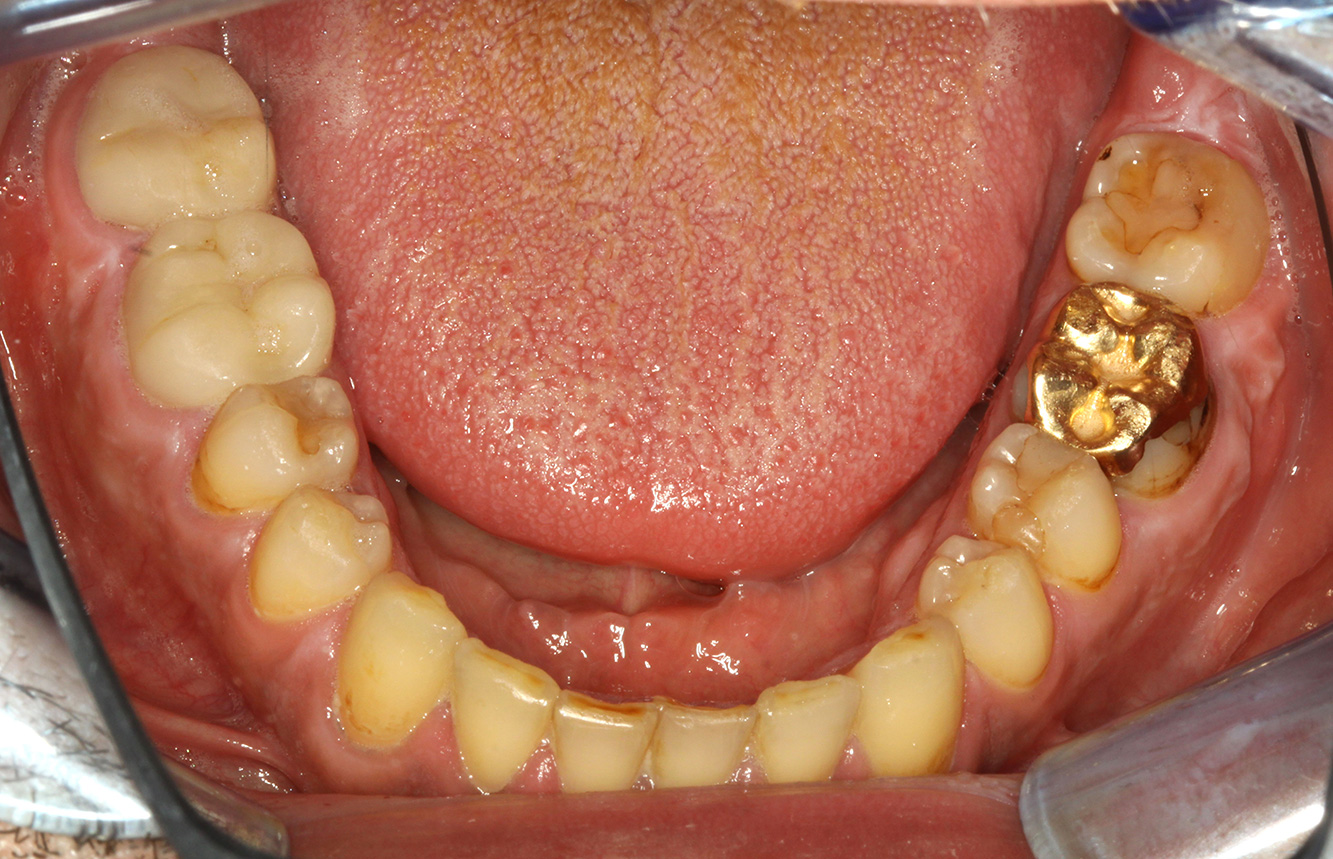

In the medical history, the 55-year-old patient states that he has no systemic disease and is not taking any medication. The patient’s lifestyle is similarly unremarkable. The patient has a few tooth restorations and two implants (2nd and 4th quadrants). On the basis of current findings, gingivitis is identified in an otherwise stable periodontal condition on the reduced periodontium (stage III, grade A). more

The healthy patient with pre-existing periodontal disease & peri-implantitis